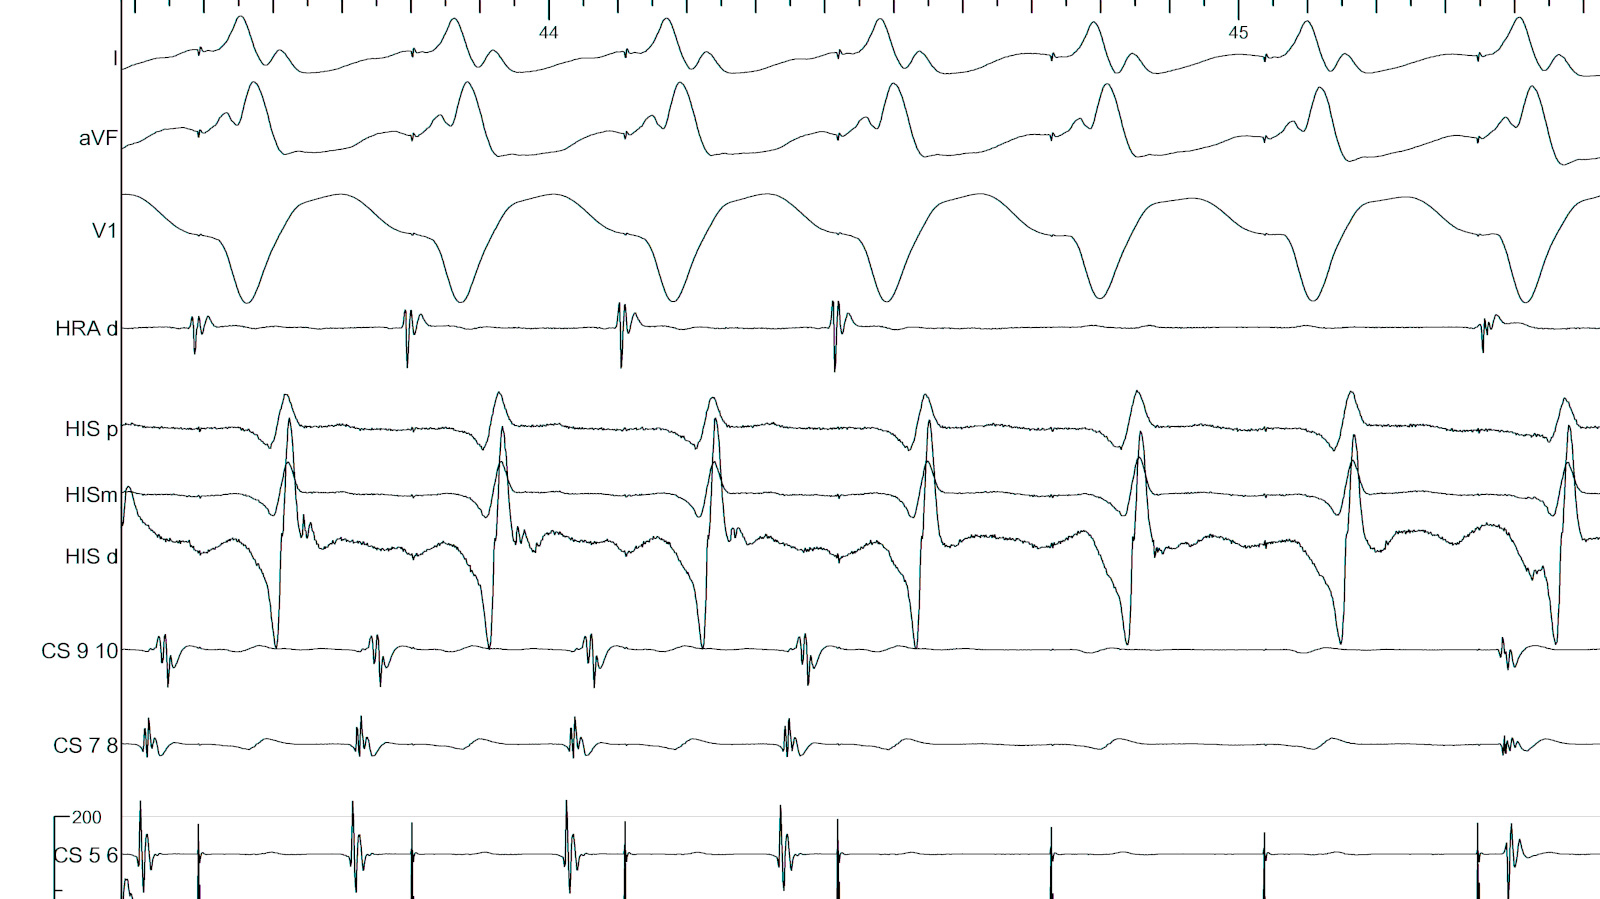

#8 When ablating in tachycardia, entrain the tachycardia

entrain_ablate.jpg